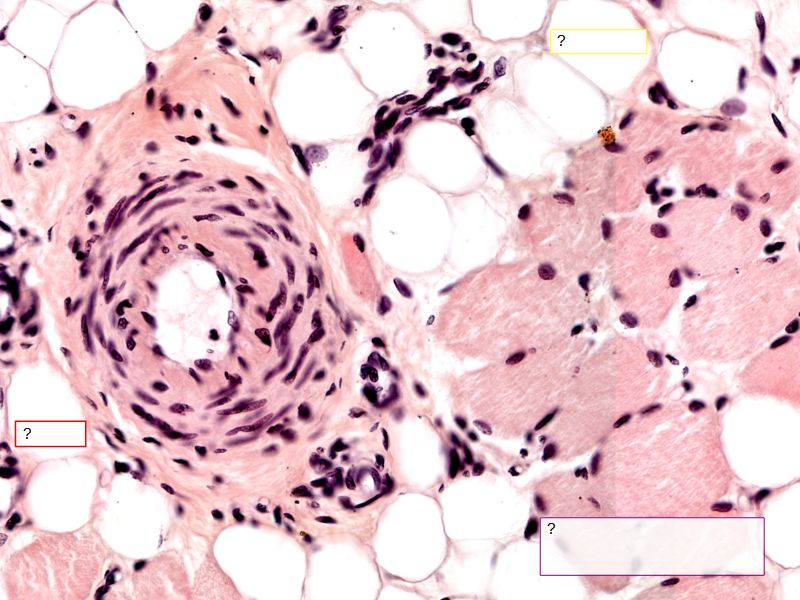

Fill in all the missing labels, and assess as you move through the slides. Answers on the down slide. It is important to do this using pen and paper, and not just glance through the images.